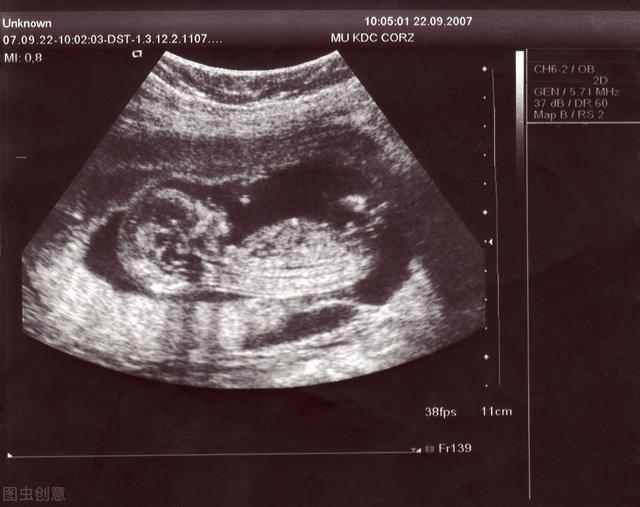

去年年初,我在计划之外怀孕了。我刚加入新公司,刚过试用期。因为这个原因,我对公司感到愧疚。而且考虑到各种因素和目前的情况,我对这个孩子要不要留下非常犹豫,和老公商量了很久。就这样我挣扎了一个多月,直到在医院的彩超上看到那个小小的心跳,我才决定留着她,因为那一刻,我突然有一种说不出来的感觉,她已经是一个有心跳的小生命了!